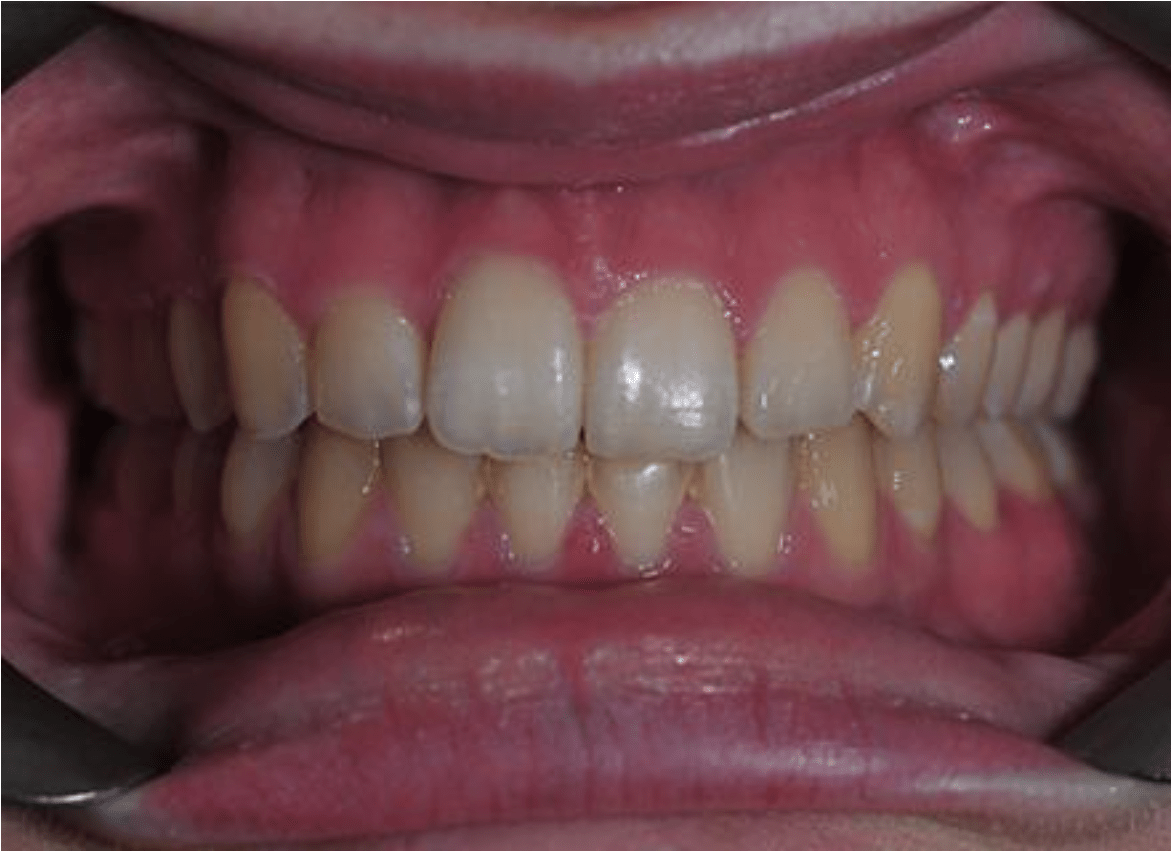

In this case, the upper incisors had a pushed back appearance and they were twisted. the smile was narrow – when the patient smiled the sides of the smile were in shadow. we used clear brackets to gently untwist and straighten the front teeth while widening the upper arch/jaw to broaden the smile. this patient was beaming for the first time in just 12 months.